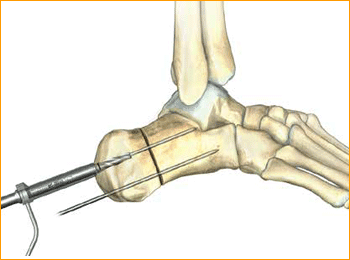

6. SOFT TISSUE GUIDE PLACEMENT

Place the soft tissue guide (the guide should be used throughout) over the guide wire and open the near cortex using the appropriate cannulated profile drill.

7. DRILL

Leaving the soft tissue guide in place, drill into the far fragment with the appropriate cannulated, long drill. Reference the markings on the drill to confirm desired depth.

Tip: The long drill is recommended to mitigate the effects of varying bone density and distraction upon screw insertion.